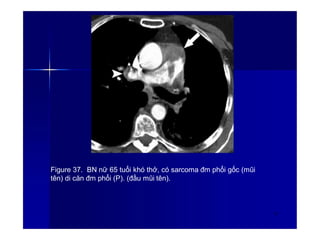

Figure 37. BN nữ 65 tuổi khó thở, có sarcoma đm phổi gốc (mũi

tên) di căn đm phổi (P). (đầu mũi tên).

52